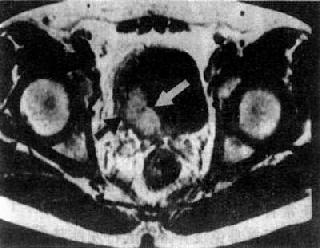

MRI检查,尤其是增强扫描较有利于早期诊断和鉴别诊断以及肿瘤的分期(图4-4-10)。

图4-4-10 膀胱癌

膀胱腔内突起的肿块(白↓),

肿瘤已侵犯至壁外(黑↑)